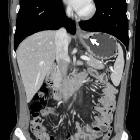

Pseudoachalasie

bei AEG-Tumor: Hochgradig stenosierender Tumor des ösophagogastralen Übergangs mit erheblicher Aufweitung des Ösophagus darüber. Es mussten zwei Stents platziert werden, um die Stenose zu überbrücken.